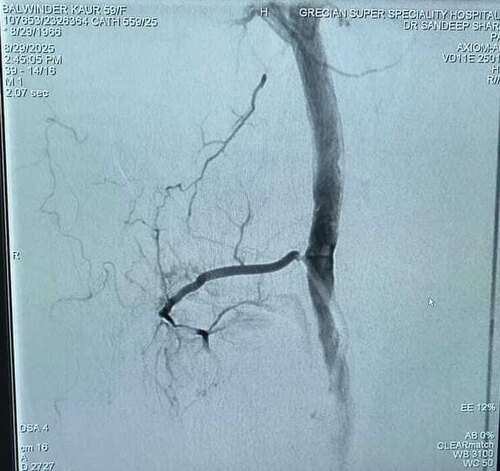

Balwinder Kaur Journey to Knee Pain Relief: A Successful GAE Treatment Story

Genicular Artery Embolization